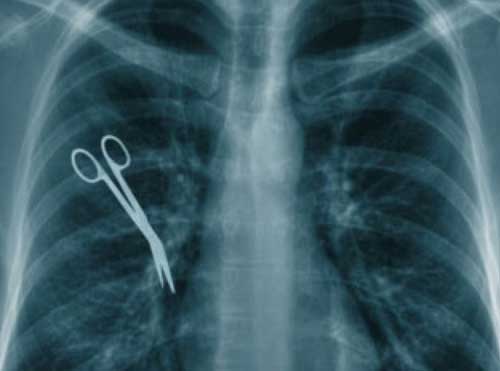

AH, QUELLO STRANO DOLORETTO DOPO UNA OPERAZIONE

Clicca per Ingrandire Garza, pinze, forbici, asciugamani, tubi di plastica: è lunga la lista degli oggetti che i medici dimenticano troppo spesso nel corpo dei loro pazienti durante le operazioni. Secondo un recente rapporto Ocse (Organizzazione per la cooperazione e lo sviluppo economico) gli ospedali italiani hanno però una buona reputazione. Rispetto a tutti gli altri paesi europei, l'Italia si piazza all'incirca a metà della classifica occupando il 6° posto su 16, avendo un numero inferiore di casi ‘denunciati’ rispetto alla media in cui inavvertitamente sono stati lasciati oggetti estranei nei corpi dei pazienti. Maglia nera della classifica generale la Svizzera, che si colloca all’ultimo posto.

Tali disattenzioni, anche se a volte vengono alla luce solo dopo anni, possono essere fatali, dice l'Ocse. La media europea è del 3,8 per 100mila operazioni. In Italia è di 3,5 mentre per l'ultima classificata si arriva all'11,6. Per fare un confronto, la Norvegia è a 6, la Germania a 5,5, la Svezia a 4,4 e la Finlandia a 3,9. Ogni tanto capita di sentire storie di pazienti sottoposti a interventi chirurgici che a distanza di tempo scoprono di avere nel proprio corpo oggetti dimenticati dai medici che li hanno operati.